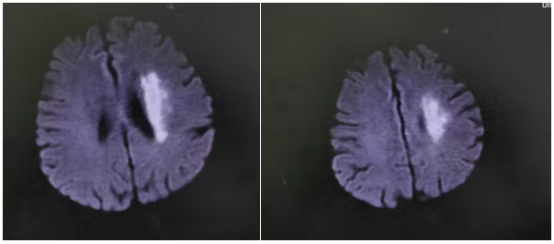

那天,71岁的符阿婆在家突发右侧肢体无力,说话也变得含糊不清。紧急送医后,检查结果令人揪心——左侧大脑中动脉M1段闭塞。

“当时情况非常紧急,”主管医生刘婷回忆道,“造影后发现符阿婆血管闭塞远端血流灌注严重不足,考虑是‘低灌注’导致核心梗死区周围的脑组织(缺血半暗带)也濒临坏死边缘。这意味着,虽然发病时间已较长,但仍有大量脑组织处在‘生死边缘’,若不立即干预,瘫痪将不可逆转。”

“时间就是大脑,虽然超过了常规时间窗,但根据最新的诊疗理念和影像学评估,我们判断患者仍存在可挽救的脑组织。”李威副主任医师解释道,“大脑中动脉全程闭塞,就像一棵树的主干被砍断,远端所有枝叶都将枯萎。我们必须尽快‘接通’主干,恢复血流。”

手术台上,一场与时间的赛跑再次开启。介入团队在DSA(数字减影血管造影)的精确引导下,将微导管、球囊等器械精准送达大脑深处闭塞的血管处。首先用球囊扩张,撑开狭窄闭塞的血管,随后成功植入一枚支架,牢牢“撑住”了病变血管,重建了血流。